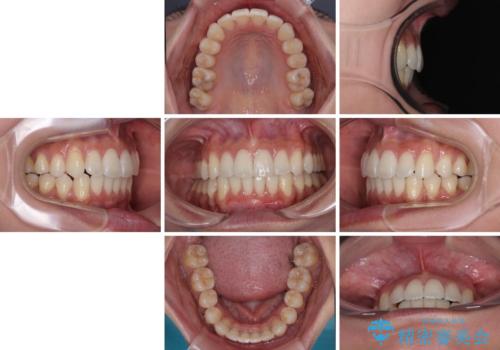

前に飛び出した上顎前歯をスッキリと引っ込める ワイヤー装置での矯正治療

横顔は元々突出した印象ではなかったのですが、上顎前歯の角度が改善したことで、唇の閉じにくさが改善されました。